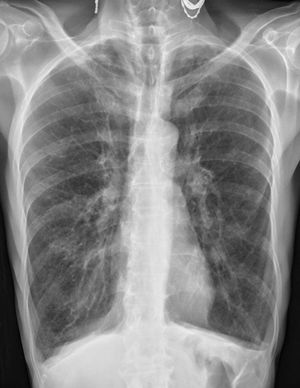

81 yr old male with 40 pack year smoking history presents to the emergency room with progressive dyspnoea and a chronic productive cough. On exam, the patient is cachectic with an increased AP diameter and his lips appear dusky. His oxygen saturation is 81% on room air and he has difficulty speaking in full sentences. Chest X-rays and CT scan done, what is the diagnosis?